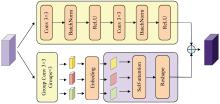

结合多尺度与注意力机制的脑组织分割方法

Brain tissue segmentation method combining multi-scale and attention mechanisms

针对脑皮层下组织部分结构(如纹状体)在医学影像中目标小、对比度低,图像分割难度大,在自动医学诊断中应用比较困难的问题,本文基于深度学习的方法提出了一种医学图像分割网络,在磁共振成像中分割组成纹状体的苍白球、尾状核、壳核3部分。本文提出的网络模型具有捕获全局和局部特征的能力,并建立了全局与局部信息的相关性,在深度不退化的同时有效融合不同尺度的深层语义特征和浅层细节特征,实现对纹状体的精确分割。模型在公开的脑部数据集上进行了验证,并与其他先进的方法进行对比,结果表明本文的戴斯相似系数、平均交并比、95%豪斯多夫距离分别为94.26%、90.94%、3.82,均优于其他几种方法,达到了先进水平,这表明本文模型可以提高对纹状体的分割精度,为相关疾病的研究提供依据。